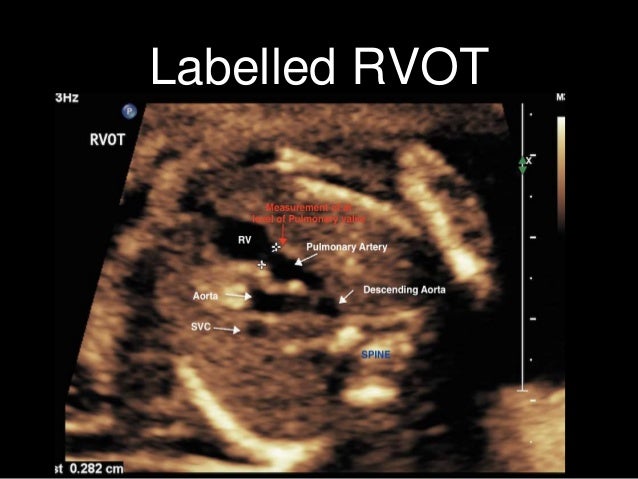

Original Resolution: 1500x512 Fetal Echocardiography Your Unborn Baby S Heart American Heart Association Fetal heart ultrasound is used to view your unborn baby's heart, assess fetal heart circulation, flow of blood in the various chambers of heart and fetal heartbeat.